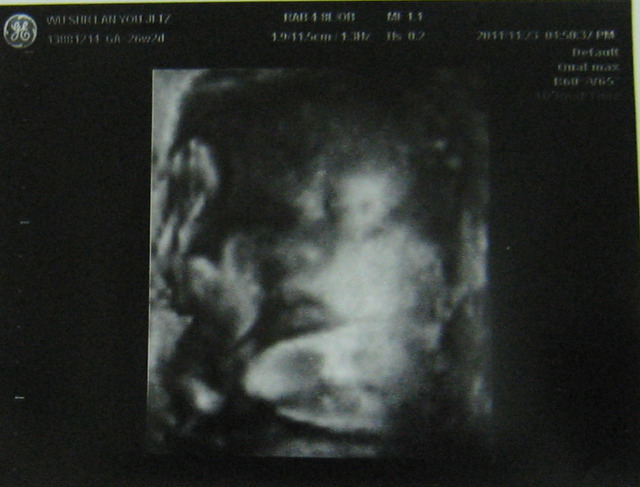

有,次也做4D,然我看到的是模糊的影像,但有次看到瓦力正在打哈欠?的子,我得好好玩,也很多人有看胎在肚子打哈欠(嘴巴)的子,所以跟大家分享。往下看就找到喔。